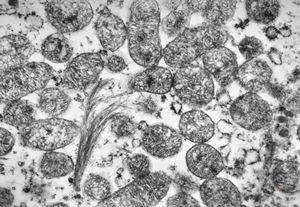

normal kidney - mouse(endothelium and podocytes)

normal kidney - mouse(endothelium and podocyte)